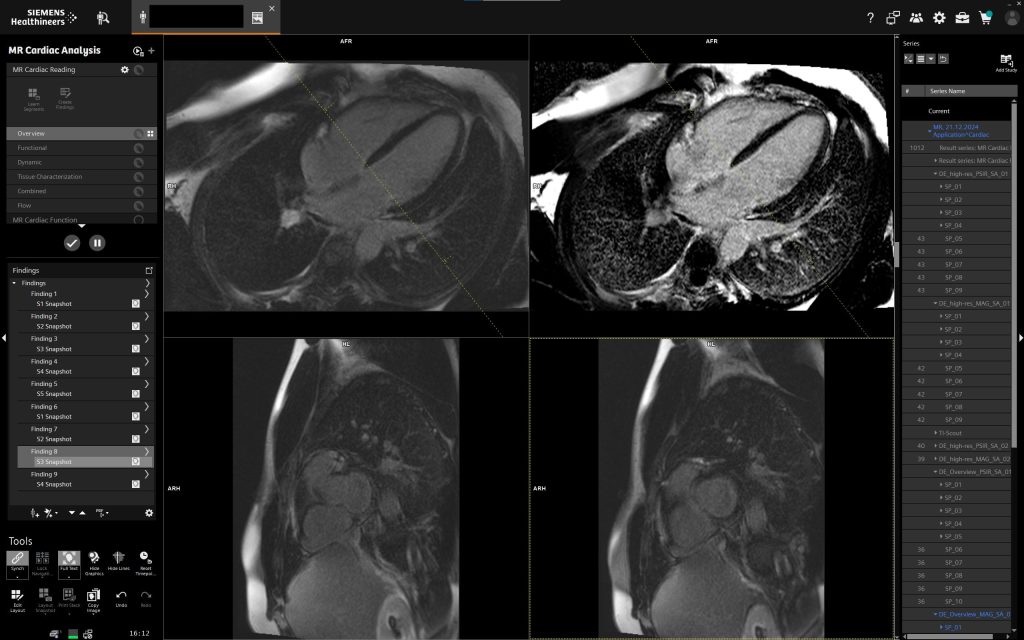

У клініці «Церебрум» МРТ серця представляє собою передовий неінвазивний метод, що дозволяє отримати надзвичайно точні дані про анатомію та функціональний стан серця.

Використання потужного магніту Siemens QS (45/200) із 16 канальною спеціалізованою серцевою котушкою та подальшою постобробкою на робочій станції Siemens Via забезпечує найвищий рівень діагностичної точності, недосяжний для традиційних методів дослідження.

- Сучасні технології обробки зображень та оперативне отримання результатів — високоякісні 3D-знімки та швидке формування детального висновку забезпечують прийняття точних клінічних рішень у найкоротші терміни.